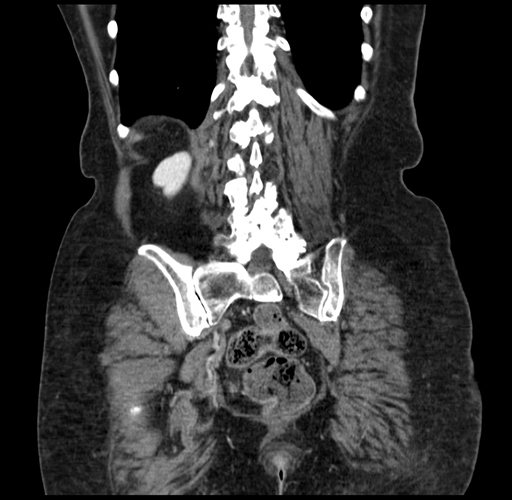

Pre-Chemo: Coronal Venous

Coronal Venous